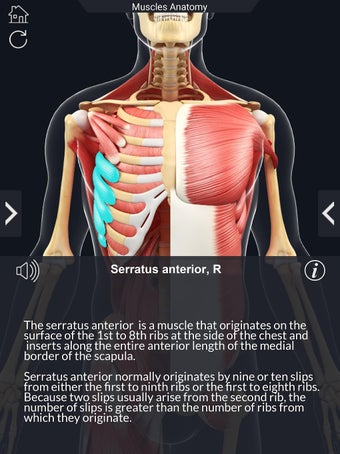

Det finns mycket detaljer tillgängliga för varje muskel, vilket gör det till ett utmärkt verktyg för medicinstudenter.

Det finns många verktyg tillgängliga för varje muskel, inklusive:

- Göm och visa varje muskel separat.